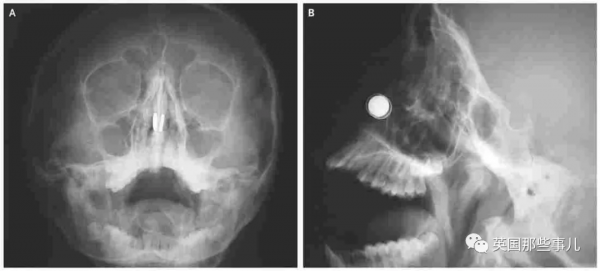

按理說,拿掉外頭的磁鐵,裡面的就主動掉出來了,誰知道,壞就壞在博士生知識過於博學,使用了磁性極強的釹磁鐵,是現今磁性僅次於絕對零度鈥磁鐵的永久磁鐵,所以當他相同的操作後,鼻孔裡的兩顆磁鐵竟然吸在了一起......X光片可見:

圖源:英國那些事兒